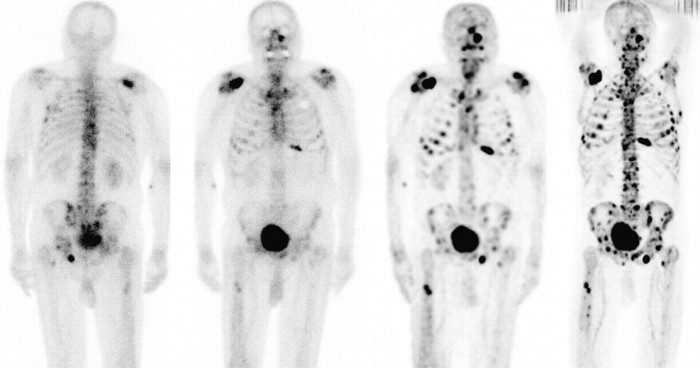

Bel ağrısı ya da yaygın kemik ağrılarında prostat kanserinin kemiğe sıçramasından şüphe edilir. Bu durumda öncelikle kemik sintigrafisi çekilir. Kemik sintigrafisi iskelet sistemini oluşturan tüm kemikleri gösterir. Kanserin sıçradığı kemikler koyu siyah noktalar şeklinde fil üzerinde görülür. Bazen geçirilmiş kemik kırıklarında da benzer görüntüler elde edilebilir. Böyle durumlarda o bölgenin MR filmi çekilir.